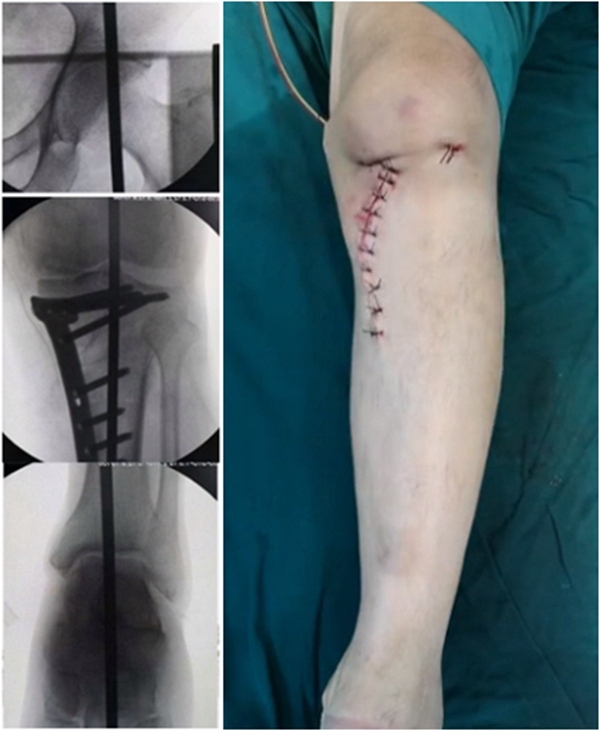

术中先打克氏针确定截骨方向,先做关节内截骨,截完后测量下肢力线,发现并没达到术前设计的Fujisawa点。

术中影像资料

随后用骨刀继续向前敲,做HTO内侧开放楔,截骨完成后内侧固定,并测量下肢力线,此时达到术前设计的要求。

该患者撑开较大,取了髂骨进行植骨。

髂骨植骨

最终力线

术后检查证实达到了术前预期的手术效果,关节线达到了平行,半脱位得到矫正,同时关节线和地面水平。病人行走达到了理想的效果。

术后X线

患者术后4个月截骨愈合,膝关节稳定维持得非常好。

术后4个月